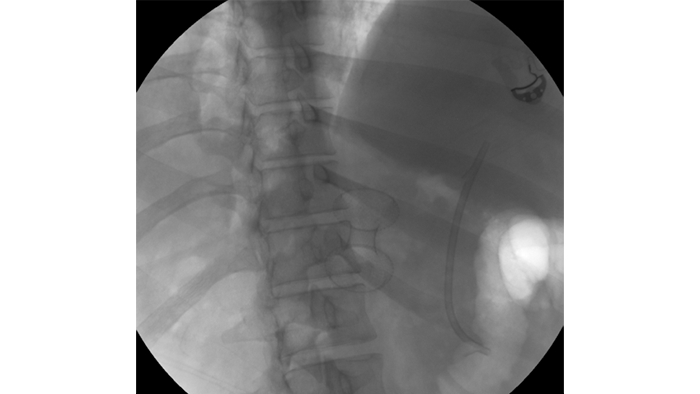

A CT scan was performed six weeks later showing WON formation with liquefaction, as well as good apposition to the posterior wall of the stomach. The patient was referred for EUS-guided transluminal AXIOS™ Lumen Apposing Metal Stent (LAMS) placement/cyst gastrostomy.​

Using the AXIOS Stent, the WON was accessed via a transgastric route. A 20mm wide and 10mm long AXIOS™ LAMS was deployed across the gastric wall.​